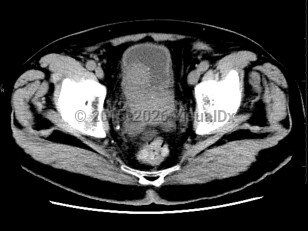

Prostate cancer

Most prostate cancers are identified at the local stage through annual screenings, and the majority of patients are asymptomatic at that stage. At later stages, physical findings may include perineal pain and urinary changes (eg, frequency, retention, nocturia). Urinary changes in men are more frequently the result of benign prostate conditions, which are sometimes found as comorbidities. Physical examination may reveal areas of induration, asymmetry, and/or prostate nodule. Diagnosis is confirmed via prostate biopsy.

If cancer has spread, physical findings may include bone pain or pathologic fracture. See metastatic prostate carcinoma.